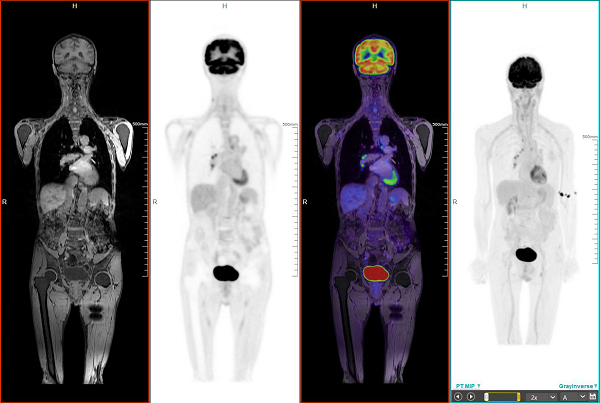

聯影一體化PET/MRI人體成像系統

掃描案例:PET/MRI全身成像